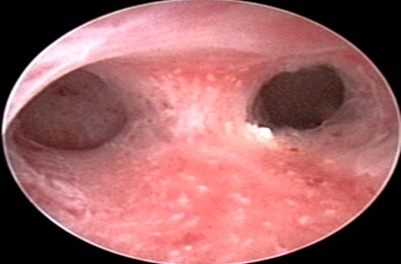

Hysteroscopy showing Septate Uterus.

Hysteroscopy showing Subseptate Uterus.